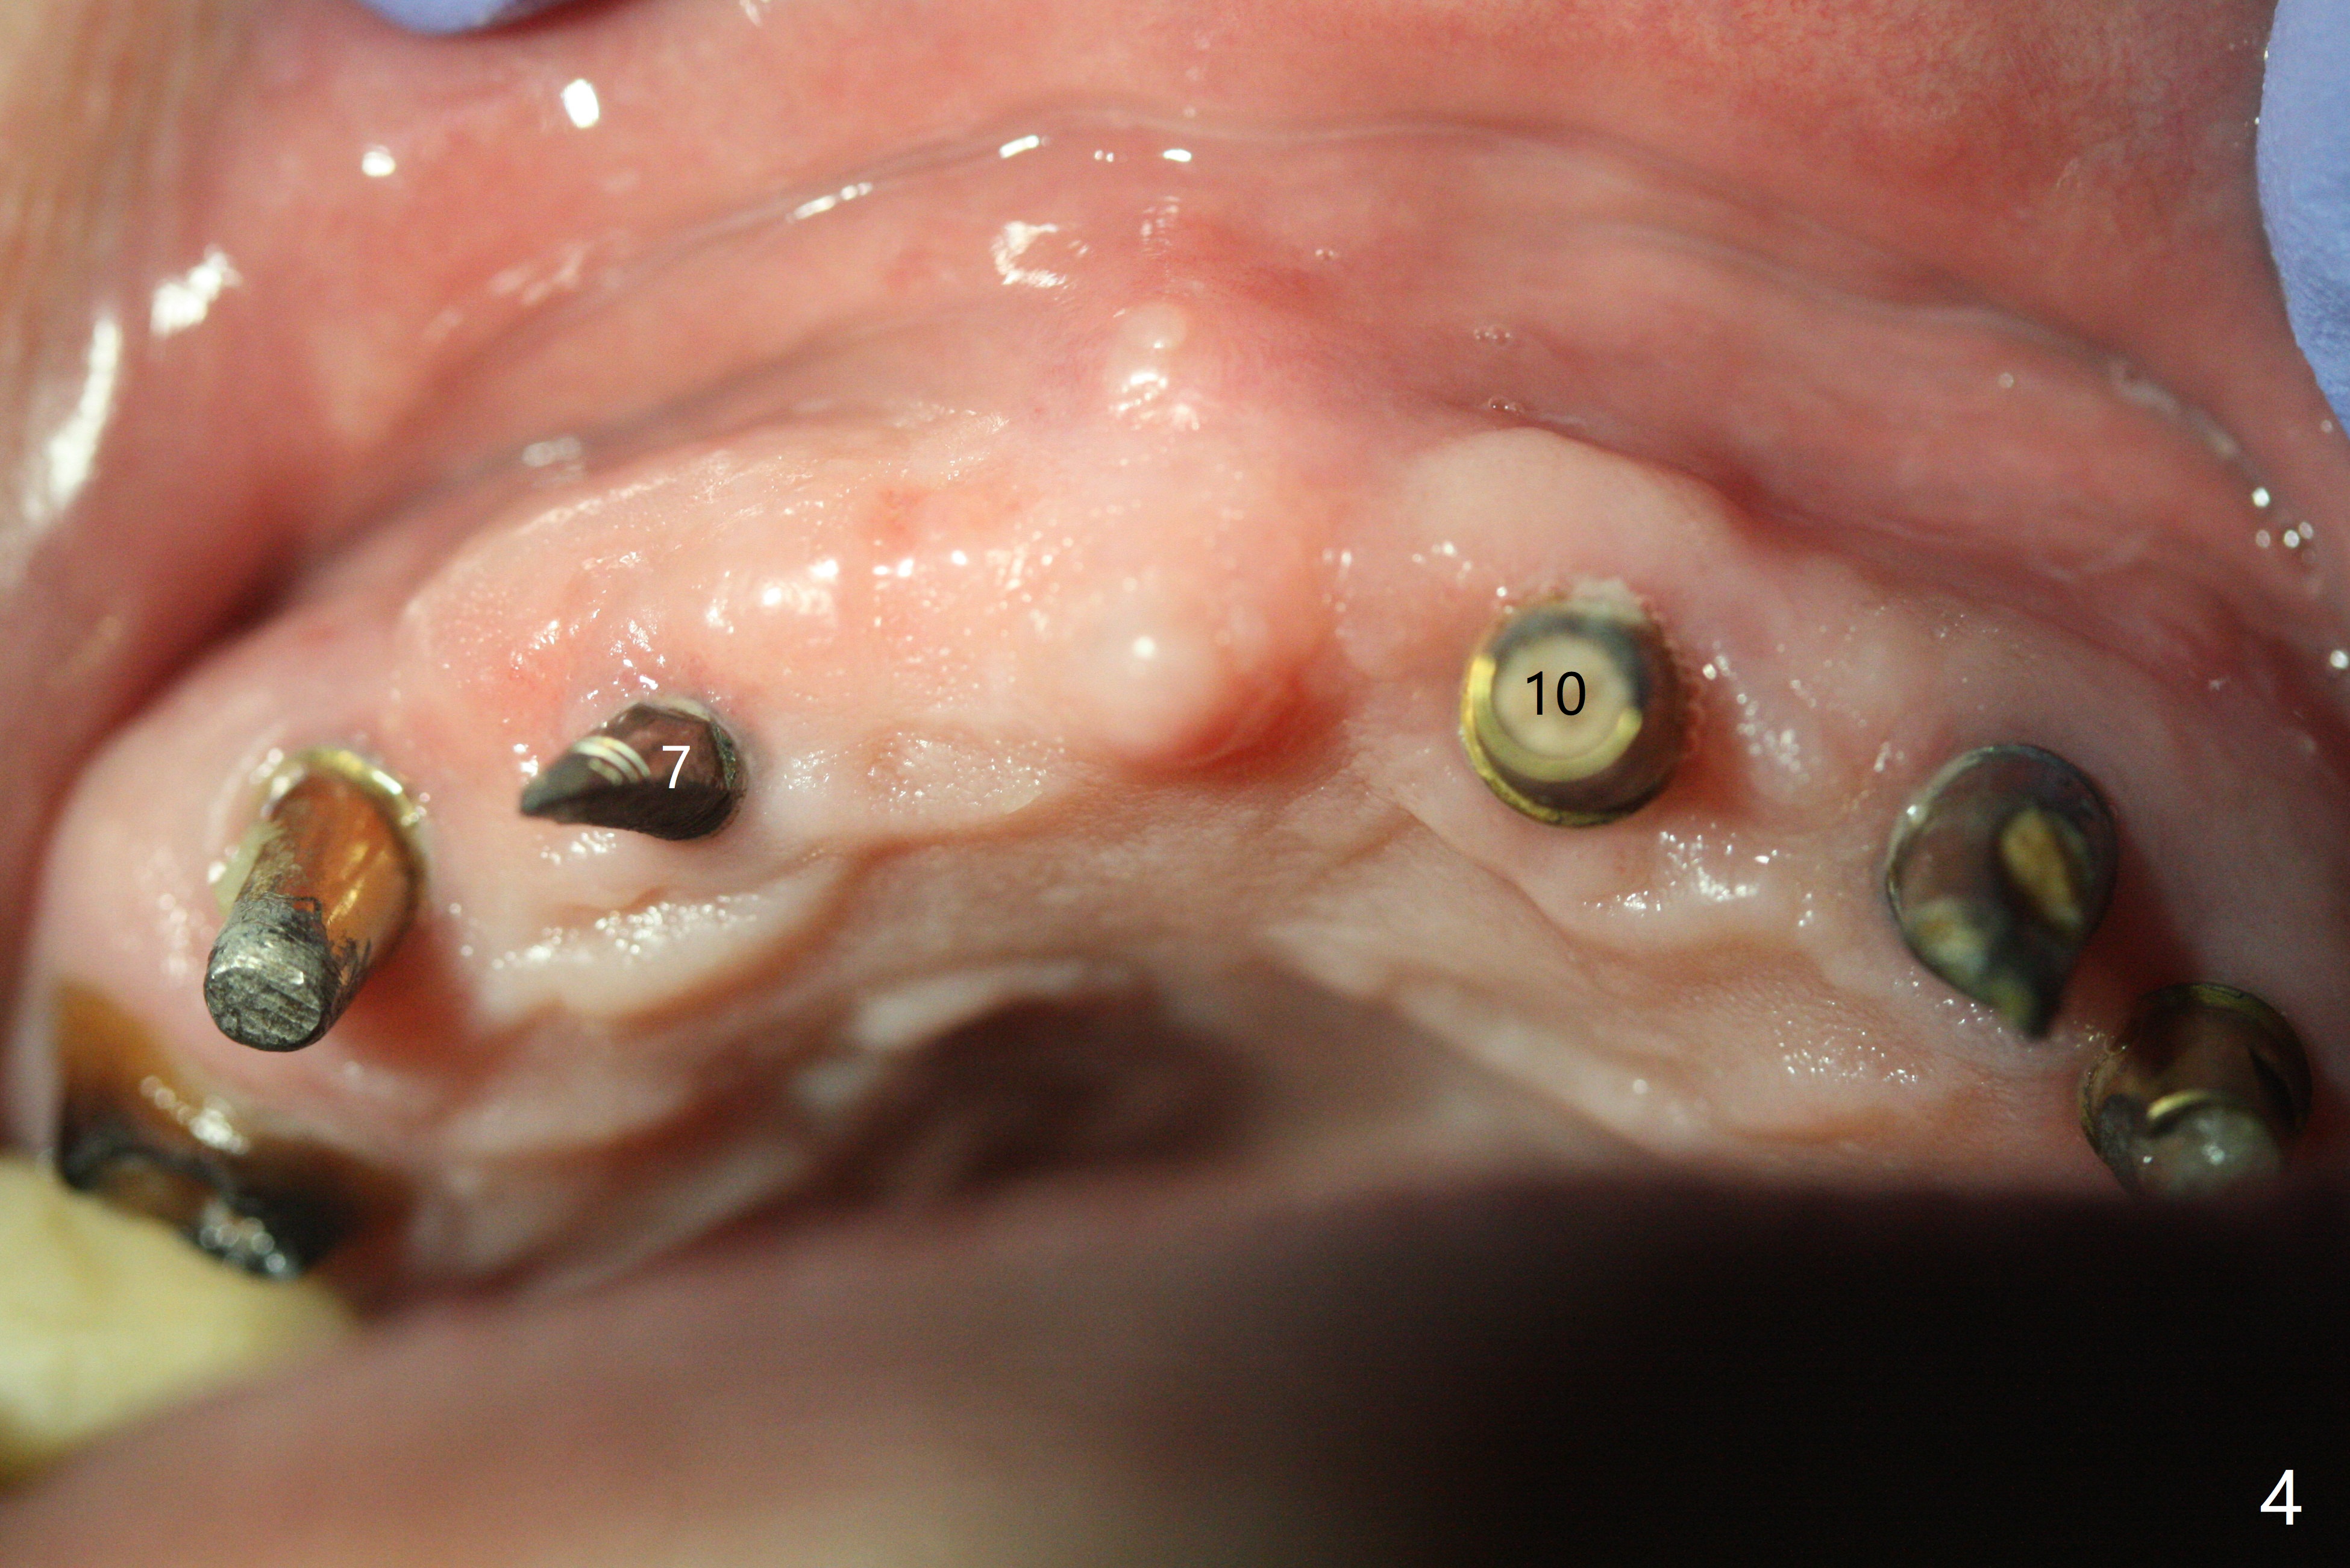

With temporarization of #3,4,13-15 (Fig.1), the anterior clearance is maintained (Fig.2). When provisional is removed, there is no papilla between #7 and 8 (Fig.3,4). After confirmation of complete seating of the abutments at #6 and 10 (Fig.5,6), gingivectomy is conducted with Diode laser (Fig.7,8). Following provisional being relined and modified, the anterior papillae form (Fig.9).